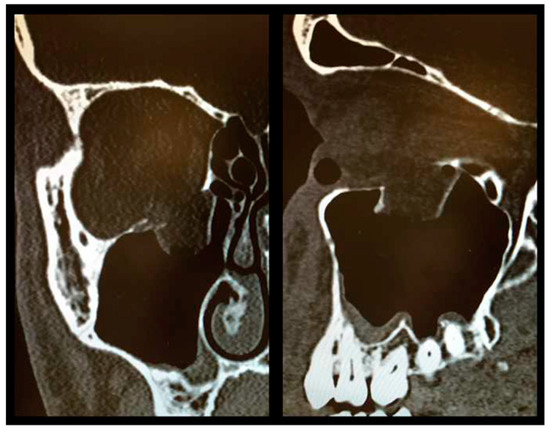

As described above, all patients underwent a first ophthalmologic examination on the day of admission. Following the decline of the frequently present periorbital swelling, all patients had a detailed orthoptic assessment preoperatively. The mean time elapsed from injury to the detailed orthoptic assessment was 1.93 days (SD = 1.45; range: 0–7 days). The mean time between the day of injury and the surgical repair using Ethisorb® patches was 4.33 days (SD = 2.71; range: 0–13 days). A representative example of a typical case is illustrated in Figure 2 and Figure 3 showing both the pre- and postoperative CT scans.

Figure 3.

Postoperative CT scan following OFF reduction and placement of Ethisorb® ((left) coronal view, (right) sagittal view).